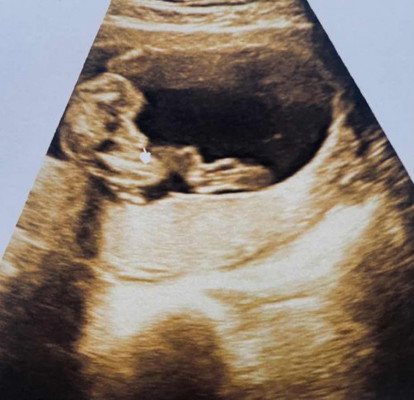

18 week 2 day

ภาพนี้เป็นผู้ชายไหมคะ แม่ไม่มั่นใจ ดูไม่ออก มองไปมองมาเหมือนนิ้วหรือเปล่า 55555 🤣 คุณหมอบอกว่าน้องมีไข่ เพศชาย

เหมือนจู๊ดจู๋เลยค่ะ